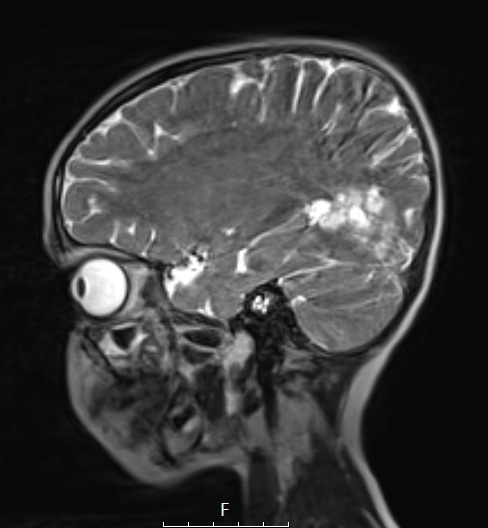

The lesion also is multinodular and hyperintense in this T2-weighted scan as seen in sagittal sections.